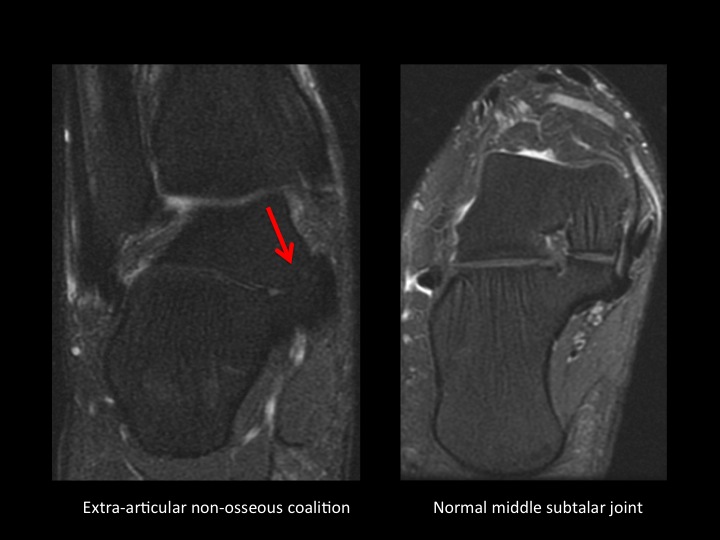

There is an accessory articular facet of the medial talus posterior to the middle facet, with non-osseous extra-articular talocalcaneal coalition (slides 1-2). In slide 3 there is an accessory ligament Ive not seen connecting the lateral tubercle of the posterior talar process and the posterior calcaneal tubercle, with surrounding synovitis (slide 4); does this have a name? As a side question, is there a consensus as to what the cyst-like changes are deep to the angle of Gissane in the calcaneus? Do you all report this? I consider this incidental, does anyone disagree?

talocalcaneal joint ( RID3030 )